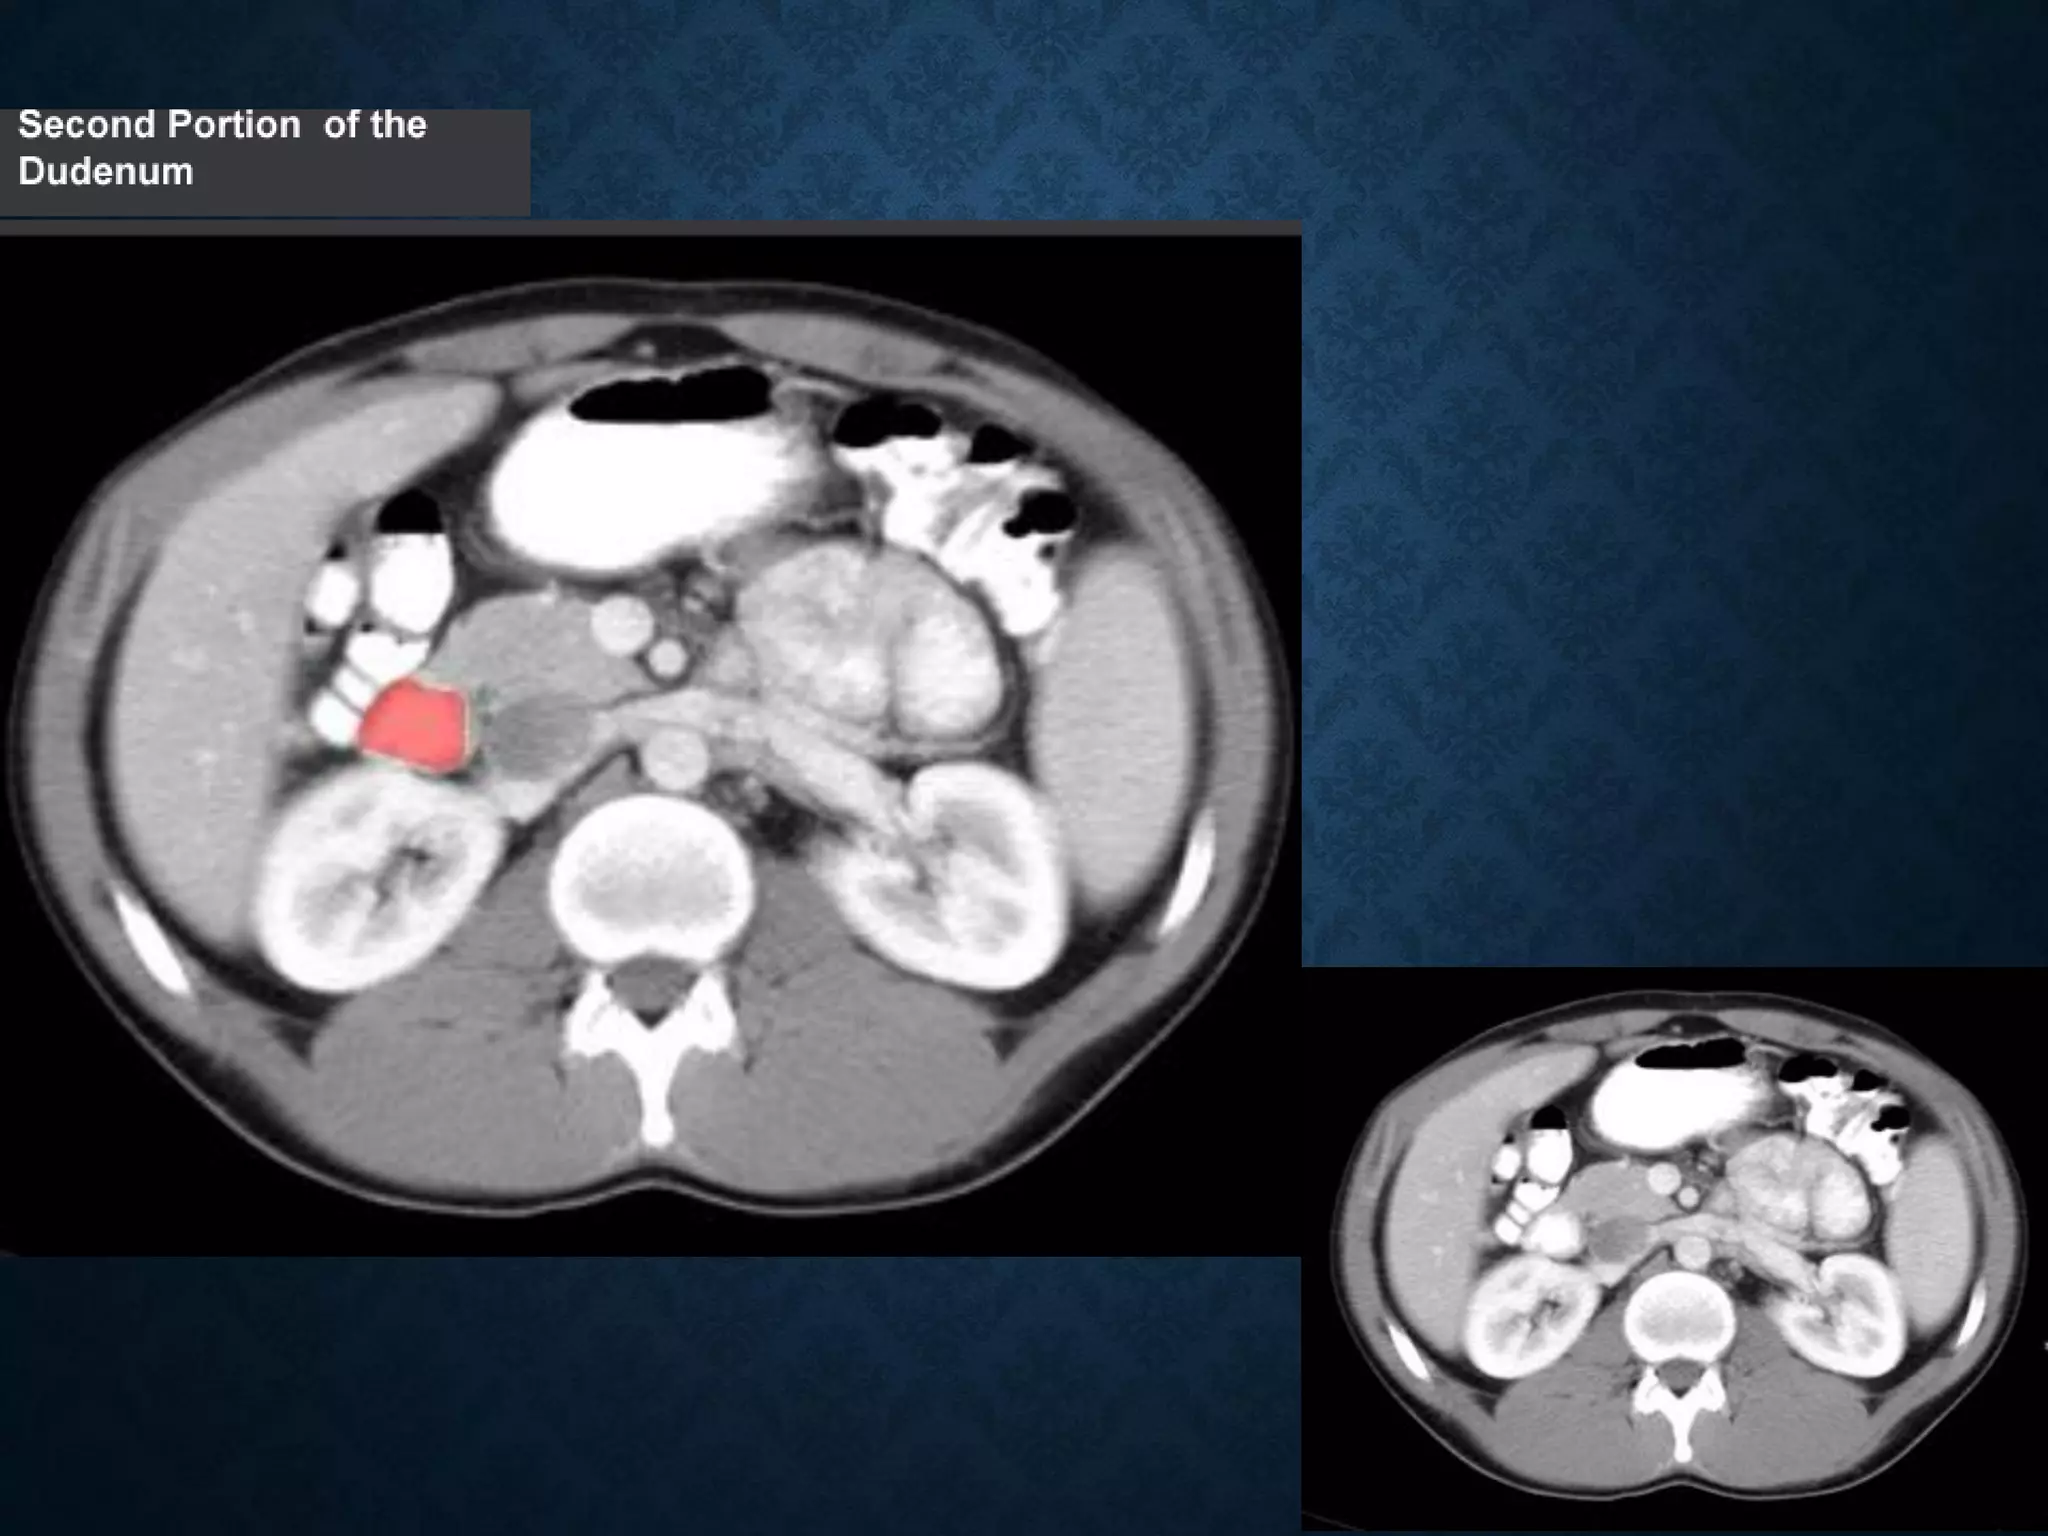

Identify the following structures in the body CT to the right. To view the location of the structure in the image click on

the label at the left and the structure will be indicated in the image. Abdominal CT scans typically begin just above

the diaphragm, so the first slice you see is of the lower chest.